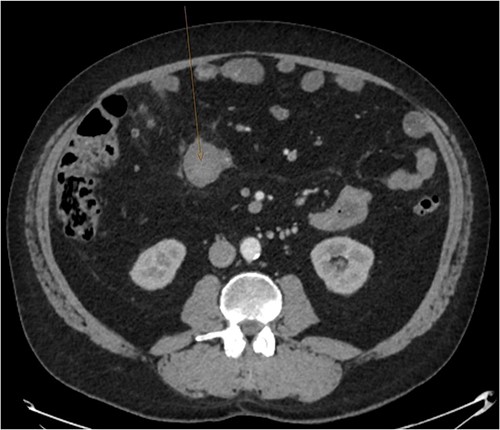

A CT abdomen-pelvis (CT-AP) revealed an acute haematoma inferolateral to the third part of the duodenum and another at the root of the mesentery. High density fluid related to the mesenteric bleed was also seen extending from the right para-colic gutter into the pelvis and in the peri-hepatic region. The patient was admitted under general surgery, stabilized with intra-venous fluid resuscitation, co-amoxiclav and metronidazole and cross matched for four units of blood. A CT-angiogram demonstrated acute haemorrhage throughout the abdomen with a 104 x 62 mm haematoma arising centrally at the level of L2 within the mesenteric fat (Fig. 1). The haematoma did not appear to originate from any specific mesenteric vessels but was related to some mid and distal jejunal loops. The angiogram also showed discontinuity when tracing the proximal and mid jejunal loops inferiorly, extensive haemorrhagic peritoneal fluid around the liver extending inferiorly (Fig. 2) and a small amount of peri-splenic haemorrhagic fluid. Curved reformatting of the angiogram revealed no abnormalities within the superior mesenteric artery (Fig. 3).

CT angiogram showing a peri-hepatic haematoma. Figure 2 is an axial section taken from the patient’s initial CT angiogram of the abdomen and pelvis. A large crescent shaped peri-hepatic haematoma is highlighted by the arrow displayed.